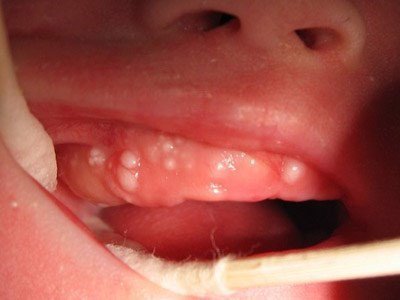

Các biểu hiện lâm sàng chẳng hạn như một hay nhiều nốt màu trắng hoặc vàng nhạt ở nông ngay dưới bề mặt niêm mạc lợi hàm trên, hàm dưới của trẻ. Kích thước mỗi nang này thường vào khoảng từ 2 – 3mm. Nanh thường tự vỡ và tan biến mà không để lại dấu vết.

Khi bị nhiễm khuẩn, nanh vẫn có màu trắng nhưng niêm mạc lợi xung quanh rìa đốm trắng sẽ có màu đỏ, sưng thậm chí còn bị loét do sang chấn, có thể có sốt nhẹ.